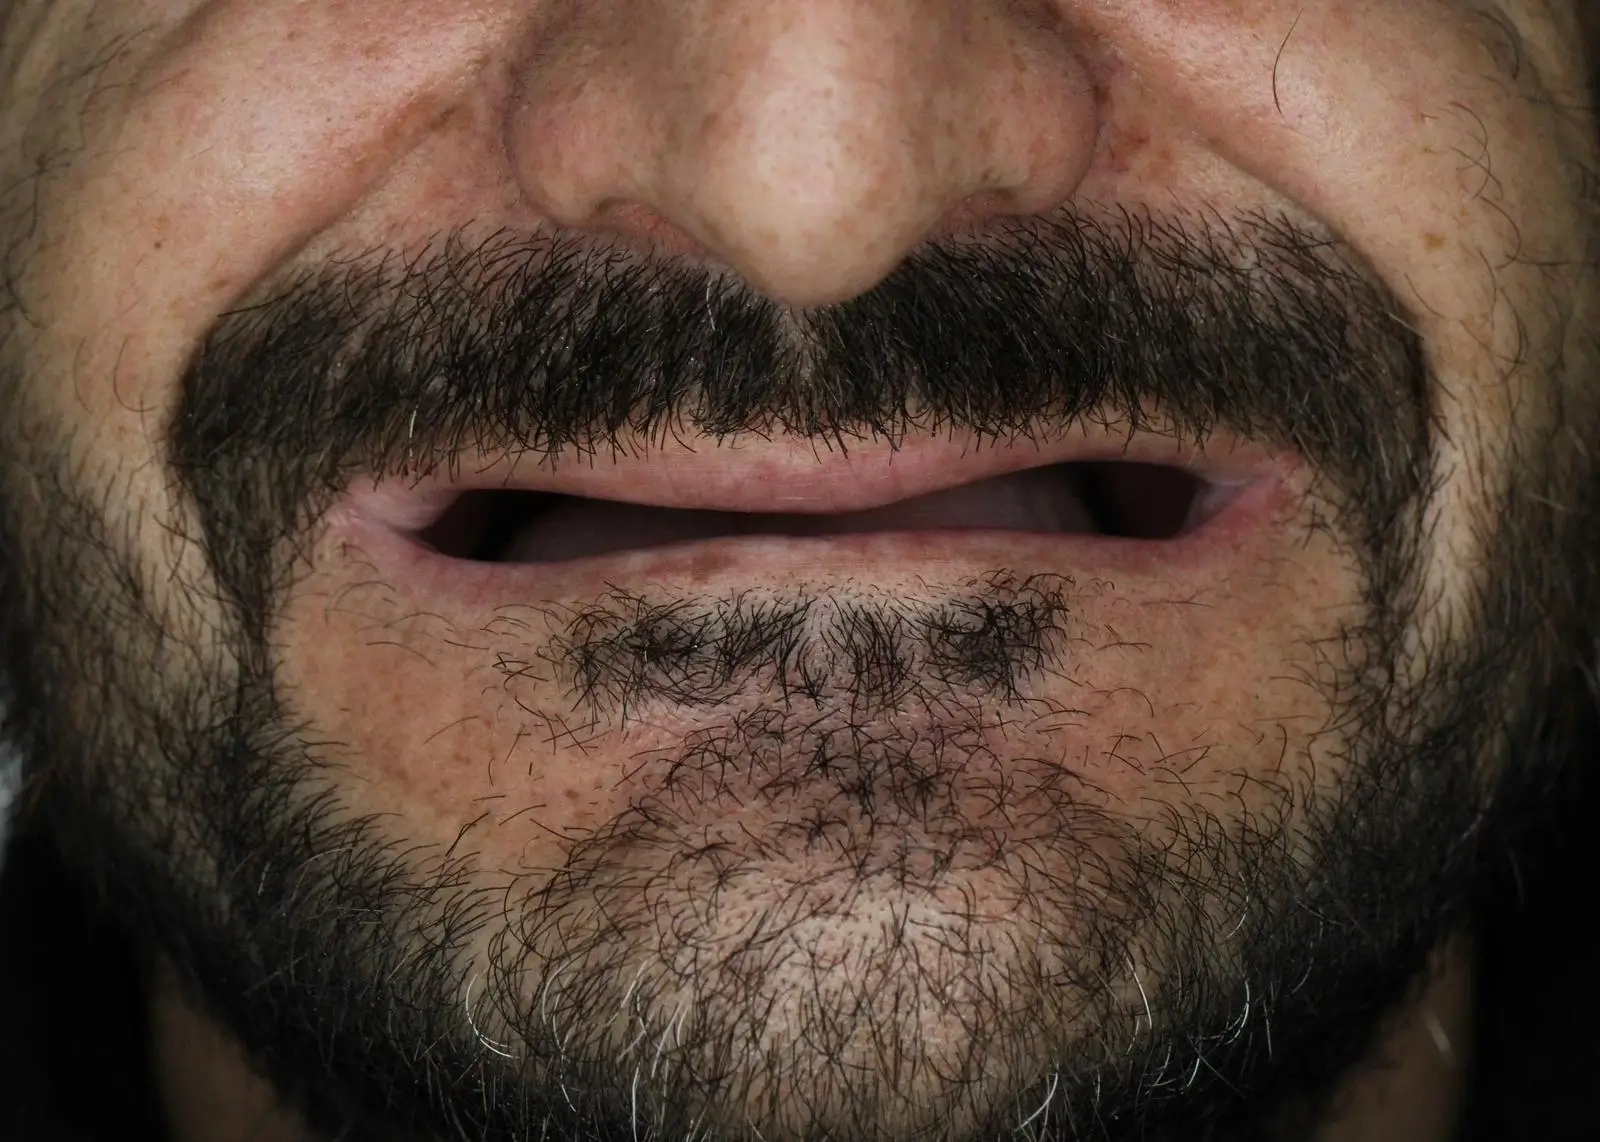

Mükemmel Gülüşe ve Sağlıklı Dişlere Kavuşanlar